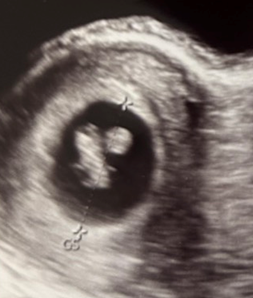

今回のエコー写真はこちら

- 妊娠週数:7週4日

- 胎芽(CRL):13.2mm

- 胎嚢(GS):25.0mm

7週4日で胎芽は13.2mm。

先週の3.2mmから考えると、とても良い滑り出しでした。